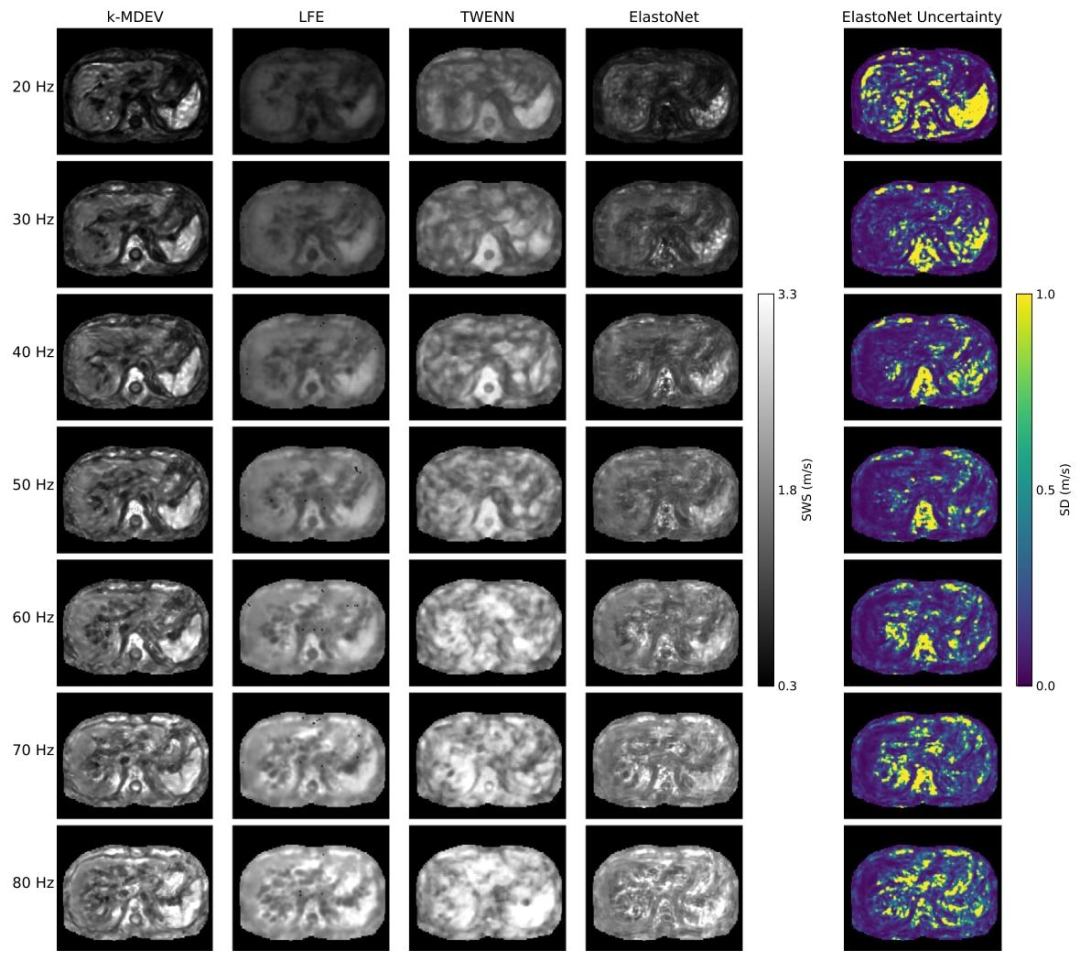

Fig. 7. Comparison of frequency-resolved SWS (shear wave speed) maps of the abdomen of a healthy volunteer produced by k-MDEV, LFE, TWENN, and ElastoNet over a frequencyrange of 20 to 80 Hz. The corresponding frequency-resolved uncertainty maps produced by ElastoNet are displayed on the right. A mask is applied to the images to suppress theair-filled regions for visualization.

图7. 健康志愿者腹部的频率分辨剪切波速(SWS)图对比 展示了k-MDEV、LFE、TWENN和ElastoNet在20至80 Hz频率范围内生成的健康志愿者腹部频率分辨剪切波速图。右侧为ElastoNet生成的相应频率分辨不确定性图。为便于可视化,图像已施加掩码以屏蔽含气区域。